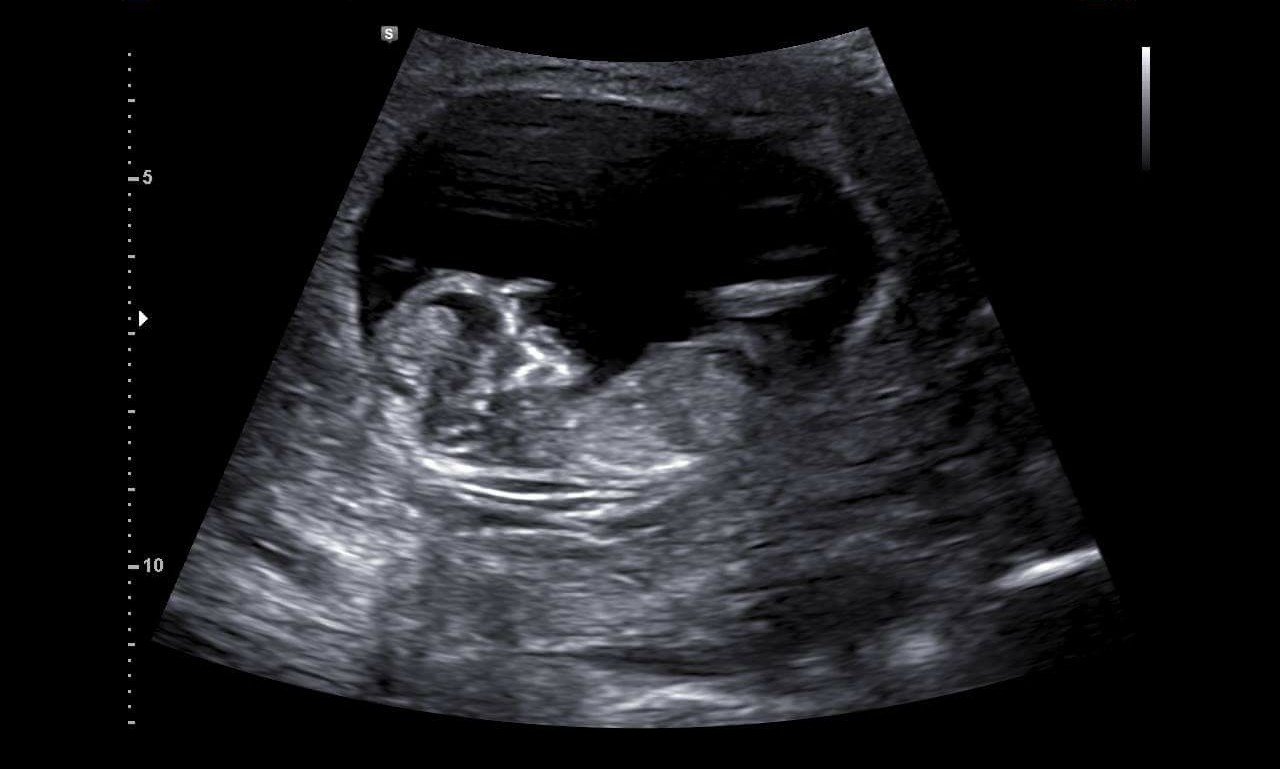

12w3d NT scan. NT results were good (as expected since NIPT was good). Pretty cool that you can see the jaws opening and closing, with what I guess are tooth buds, huh?

And so amazing (except for the tech with a pretty crappy attitude but I understand they might need to be a bit detached).

I swear that the images in real time were very much like a real baby rather than the blobby image. Due date was moved up a day, but we're still going with Jan. 14. Whole family is now calling the baby, "The Blob". Haha!